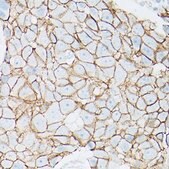

immunohistochemistry: 1:50-1:200, western blot: 1:500-1:2000

A synthesized peptide derived from human beta Catenin.